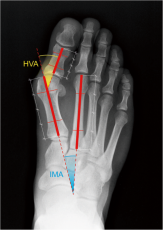

• Χειρουργικής Άκρου ποδός εστιάζοντας σε κοινές παθήσεις και παραμορφώσεις

Συμμετείχε σε ετήσια βάση, σε διεθνή ιατρικά συνέδρια όπως επίσης και σε πτωματικά σεμινάρια για την εκμάθηση νέων χειρουργικών τεχνικών. Εξειδικεύτηκε στη διάγνωση και αντιμετώπιση παθήσεων και κακώσεων με ιδιαίτερη έμφαση στη αρθροσκοπική τεχνική και την αρθροπλαστική. Σημαντικό μέρος της πρακτικής του αποτέλεσε και το ορθοπαιδικό τραύμα όπως τα κατάγματα και οι αθλητικές κακώσεις καθώς εργάστηκε ως επιμελητής ειδικός Χειρουργός σε Τριτοβάθμια Νοσοκομεία και Μείζονα Κέντρα αναφοράς Τραύματος ενεργό μέλος πολυδύναμων ιατρικών ομάδων.